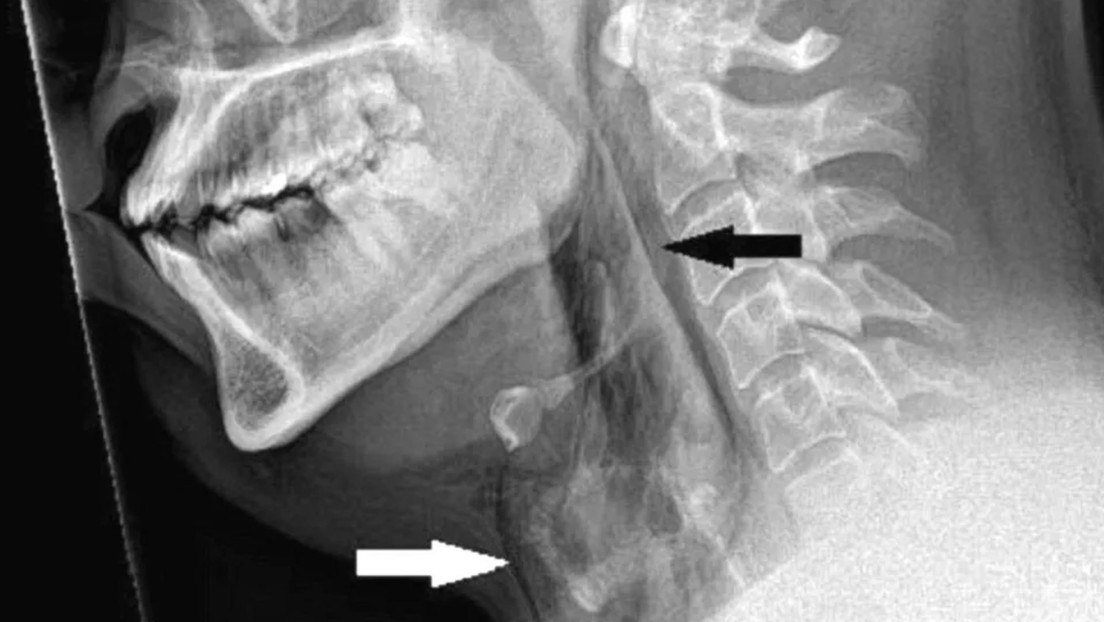

La historia, documentada este mes en la revista médica BMJ Case Reports, señala que el paciente, de unos 30 años, comenzó a sufrir un intenso dolor en el cuello inmediatamente después querer evitar un fuerte estornudo tapándose la nariz y manteniendo la boca cerrada al mismo tiempo, mientras conducía. Rápidamente acudió a urgencias del hospital Ninewells de la ciudad de Dundee, donde fue sometido a una radiografía y tomografía de cuello y tórax, que revelaron un pequeño “desgarro traqueal” a nivel de la tercera y cuarta vértebra torácica.